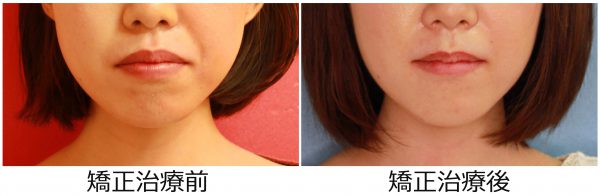

22歳 女性「 口が 閉じにくい 」( 上下顎前突症 )

22歳の 女性です

「 口が閉じにくい 、口元の出っ張りが気になる」ので治したいとの事で来院されました。

正面から見ると それほど 歯ならびが悪そうに見えませんが

横から見ると 上下の前歯が 著しく前に 傾斜しています。

このため 口もとが 大きく出っ張っています。

ご本人の悩みは「口もとが 出っ張りが気になる」そうで

この事を コンプレックスに 思われていたそうです。

また、他人からは

口もとが尖っているため ”不機嫌そう” な顔に見られがちです。

叢生を伴う 上下顎前突症 です

口元を 大きく変化させるために 上下左右の 抜歯を行い

前歯をできる限り 後方に移動させました。

2018年の2月16日にスタートして

2019年の9月13日に 終 了 しました。

治療期間は 17か月でした。

治療によって 上下の前歯は 大きく下がりました。

前歯が下がったために 口もとの 出っ張り感は 解消され

”もっさり” とした口元の印象が消えました。

口もとの 印象が 大きく変わりました

不機嫌そうな 尖った口元から スッキリとした口元へ 大きく変わりました。

ご本人の コンプレックス は解消されたそうです (#^.^#)

お口が閉じやすくなったそうです

素敵な笑顔になりました! (#^.^#)

22歳 女性 叢生を伴う 上下顎前突症 治療期間17か月 唇側矯正装置(ホワイトワイヤー)を使用した上下顎第一小臼歯抜歯治療 参考治療費 約65万円 (精密検査から終了まで) 矯正治療に伴う副作用の歯肉退縮、知覚過敏、失活、歯根吸収などは認められませんでした。